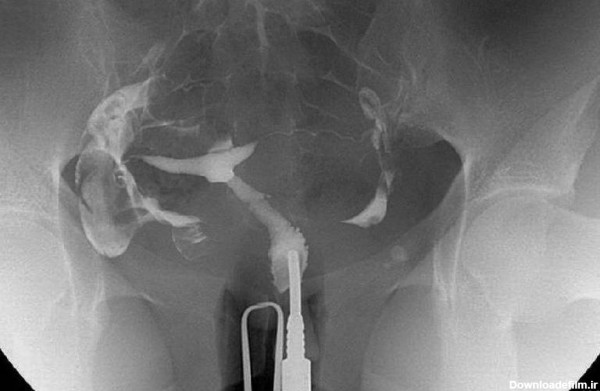

عکس رنگی رحم یا هیستروسالپنگوگرافی روشی است که به منظور بررسی داخل رحم و لوله های رحمی انجام می گیرد و انجام آن در ارزیابی ناباروری بسیار مهم است.

با توجه به اینکه عکس رنگی رحم (HSG یا عکسبرداری هیسترو سالپنگوگرافی، عکس رنگی رحم بدون درد، عکس رنگی رحم و بارداری) درگروهی از بانوان بادرد همراه بوده